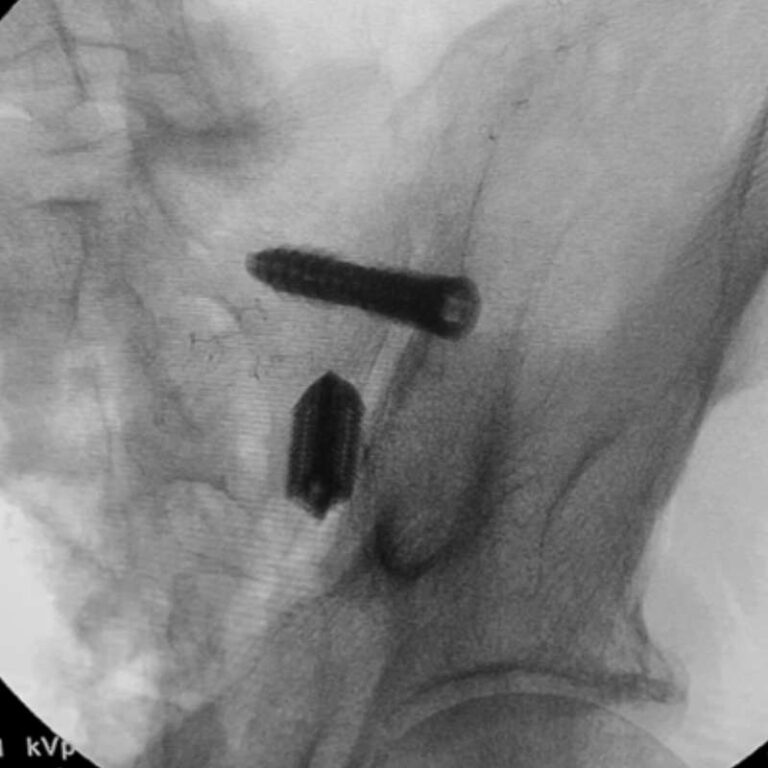

Step 3: Final Construct Evaluation

Fluoroscopy confirms implant and screw positioning. The compression threads draw the sacrum and ilium together, stabilizing the construct and promoting fusion.